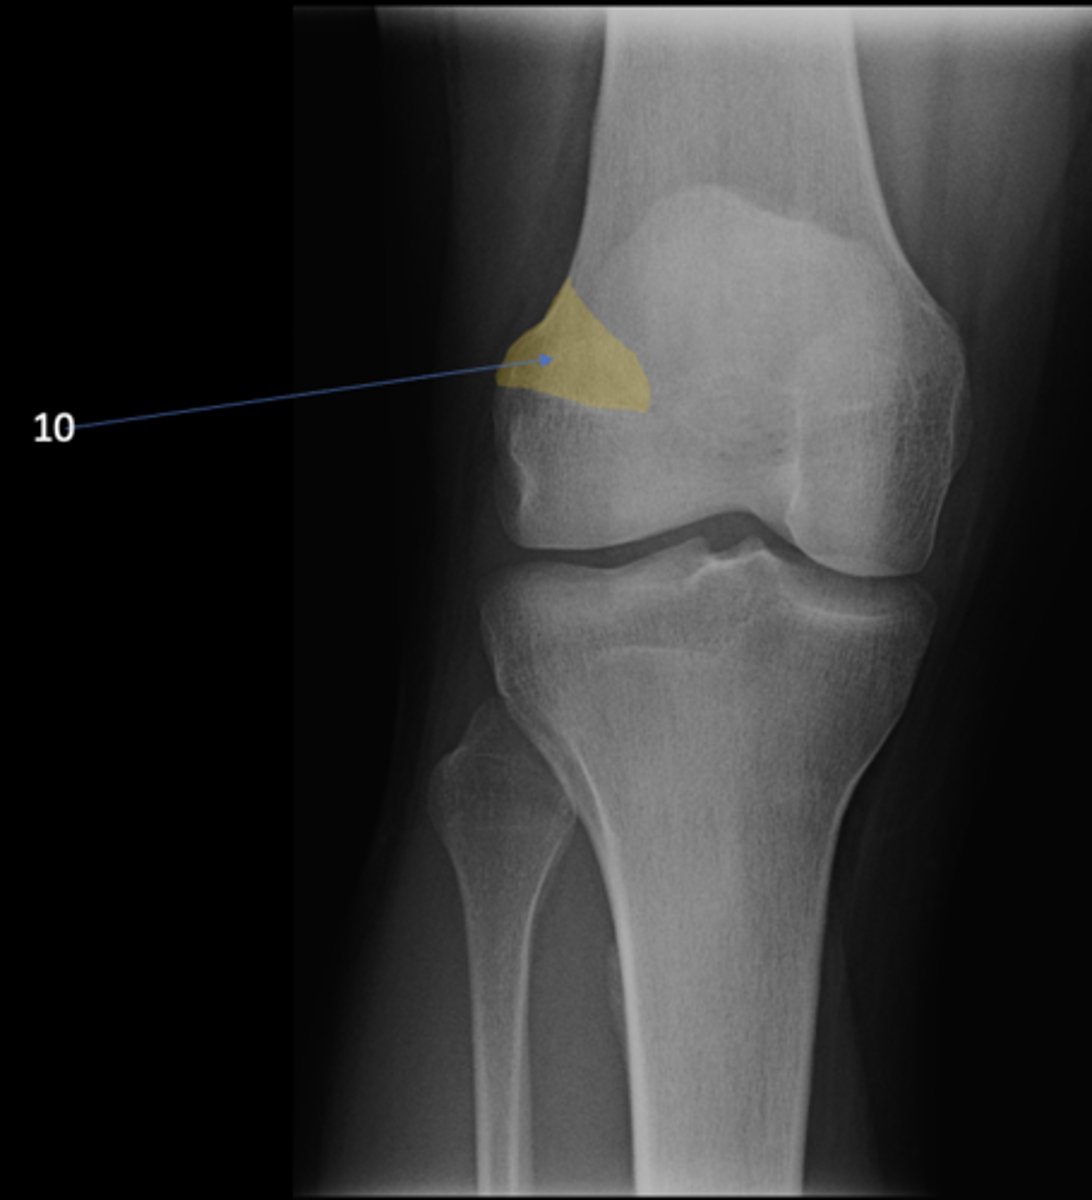

AP knee

View?

<p>View?</p>

58

New cards

Lateral femoral epicondyle

ID 10

<p>ID 10</p>